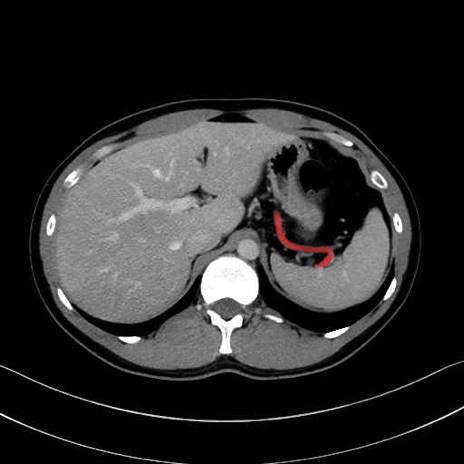

脾動脈の画像解剖

■起始:典型的には腹腔動脈幹(celiac trunk)から左胃動脈・総肝動脈とともに三分岐し、脾動脈は左後上方へ向かう。

■走行:膵上縁または膵実質背側を蛇行しながら左方へ進み、膵尾部近傍で脾門へ至る。蛇行の程度は個体差が大きい。

■終枝:脾門部で複数の終末枝に分かれ、上極・下極枝や脾門枝群を形成する。胃短動脈群や左胃大網動脈はしばしば脾動脈から分岐する。